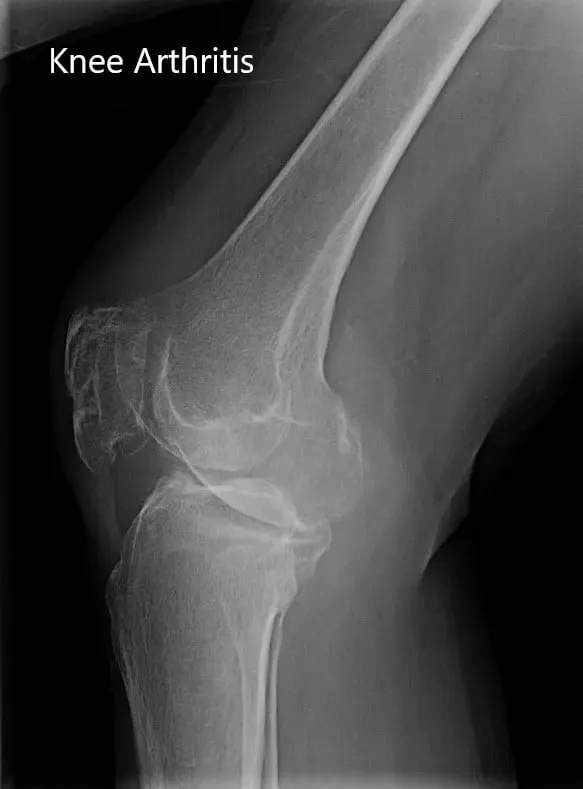

Los resultados de imagen revelaron una osteoartritis tricompartmental severa de la rodilla. Dado que su estilo de vida limita el dolor de rodilla, le recomendaron un reemplazo total de rodilla con instrumentos personalizados. Los riesgos, beneficios y alternativas se discutieron extensamente con el paciente. Él estuvo de acuerdo con el plan.

Radiografía preoperatoria que muestra la vista anteroposterior y lateral de la rodilla derecha.